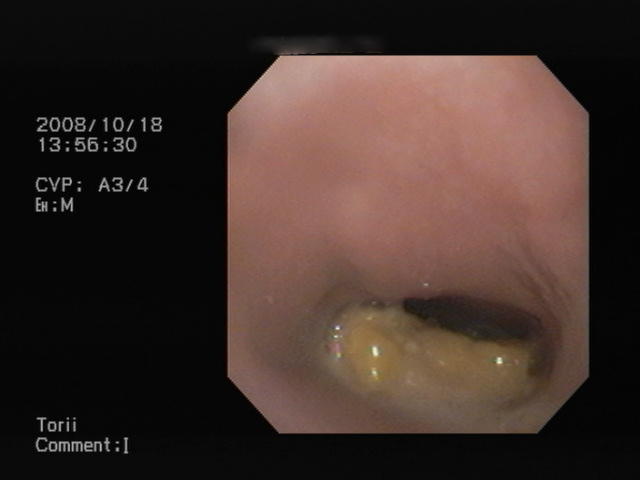

少し移動させた写真です。

食道粘膜面の炎症が分かりますよね。

赤く充血しています。(異物が引っかかっていた場所です。)

これを、内視鏡を用いて、ゆっくりと移動させました。